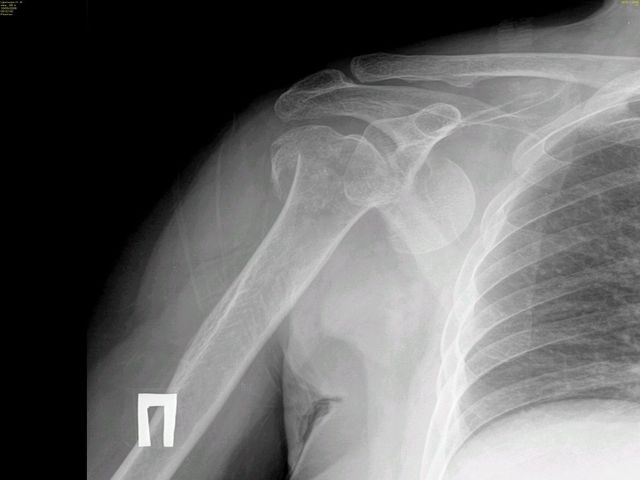

Re: несвежий переломо-вывих плеча